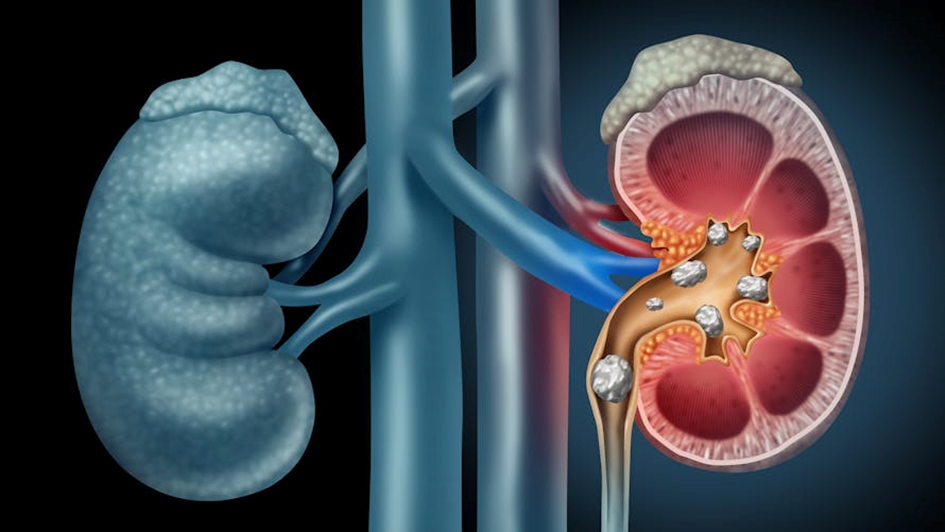

Les calculs urinaires sont des concrétions (pierres) formées par l’accumulation de sels minéraux dans les reins ou les voies urinaires. Les calculs urinaires sont une maladie en constante augmentation dans les pays industrialisés. On compte qu’un habitant sur 10 présente un calcul urinaire. Ils sont 2 fois plus fréquents chez l’homme que chez la femme.

Le traitement d’un calcul urinaire dépend de sa taille, de sa composition, de sa position dans la voie urinaire et des symptômes qu’il occasionne.

Au delà de 4 mm et en fonction de leur position, de leur densité et des symptômes qu’ils occasionnent on peut proposer différents traitements.